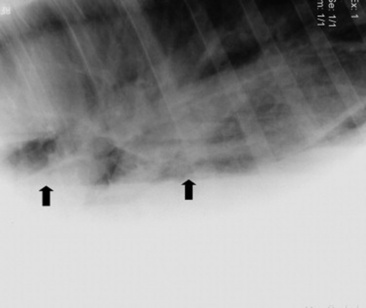

Four types of radiographic patterns are described for the thorax: alveolar (airspace), interstitial, bronchiolar, and vascular. Opaque areas coalesce and fully obliterate vessels and bronchi in the alveolar pattern; air bronchograms may be prominent. This pattern is common in pulmonary edema, pulmonary hemorrhage, EMPF, ALI, ARDS, lung consolidation, and neoplasia. Interstitial patterns are the most common patterns noted in equine thoracic radiographs and are characterized by a blurring of the edges of pulmonary vessels, a diffuse increase in lung density, and variable reticular, linear, and nodular opacities. The reticular pattern is most commonly associated with more diffuse infectious lung diseases, pulmonary edema, interstitial pneumonia, and pulmonary fibrosis, whereas the irregular linear pattern is seen most commonly with resolving bronchopneumonia. A nodular pattern is seen with abscesses, granulomata, and neoplasms. It is rare to see a pure bronchial pattern in a horse, and it usually seen in association with an interstitial pattern. An exception is paired linear opacities or numerous small circular opacities (donuts) representing thickening of large or medium airways in equine bronchitis and bronchiolitis. The vascular pattern is seen in horses radiographed immediately postexercise or in animals with left-to-right cardiac shunts. Finally, extraparenchymal problems such as pleural effusions or free gas may be seen on thoracic radiographs of large animals. Thoracic radiology may be used for evaluation of potential rib fracture but is far less sensitive than thoracic ultrasonography in this regard.

Thoracocentesis

image

Fig. 31-3 Thoracocentesis and therapeutic drainage in the horse. Pleural effusion can be large and bilateral. Samples should be obtained for culture and cytologic examination at the time the chest is drained.

Courtesy Dr. Corinne Sweeney, University of Pennsylvania, New Bolton Center, Kennett Square, Penn.